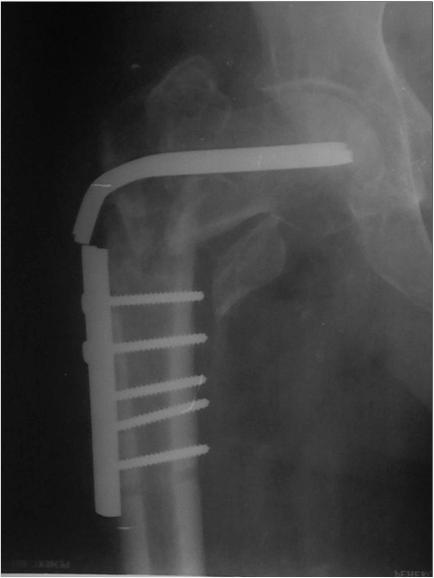

Поступил недавно из области 55-летний пациент с несращением проксимального отдела бедра (травма 4 мес. назад), после несостоятельного остеосинтеза 2 мес. назад - древняя угловая пластина, рядом спонгиозный винт через шейку бедра аж в вертлужную впадину. Внешне все тихо, аккуратный линейный рубец в вертельной области. Анализы спокойные. Во время удаления взял дважды посев (последнее время все удаления на всякий случай сеем) с интервалом минут в 20, с первого же винтика, потом из из ложа пластинки после удаления.Хотели тут же сделать реостеосинтез гамма стержнем, но укрочение и варус одномоментно устранить не удалось, поэтому оставили больного в дистракторе таз-бедро. На следующий день звонят микробиологи - в обоих посевах массивный рост клостридий. Назначили метрогил внутривенно. Через день как раз бумажка про первый посев подоспела - аж perfringens! Плюс еще какие-то стрептококки. Чувствительность есть, оба к амоксиклаву 4+, например. Cунул зонд до кости, взял оттуда посев - вроде ничего поначалу, но день на четвертый выросли опять те же клостридии. Вчера была неделя. Внешне рана спокойна. Температура нормальная. Остеосинтез если не делать - остается неопорная конечность. Так что делать надо. Растянуть аппаратом вроде удалось.Вопросы - как правильно выйти на операцию, и пройти далее? То есть ждать ли N-кратных стерильных посевов перед остеосинтезом? Если ждать, то N равно скольки? После операции - антибиотики? Как долго? Может, расшить зажившую рану после удаления, и положить туда спейсер из цемента с антибиотиками? Еще какие-то соображения-мысли-советы? Вообще, как относиться к высеванию патогенной флоры при отсутствии явной клиники? Отдельный вопрос - как отбиться от скучающих своих и внешних эпидемиологов, которые стойку на слово "клостридия" сделают так активно, что я боюсь даже последствия предполагать. Заранее спасибо.